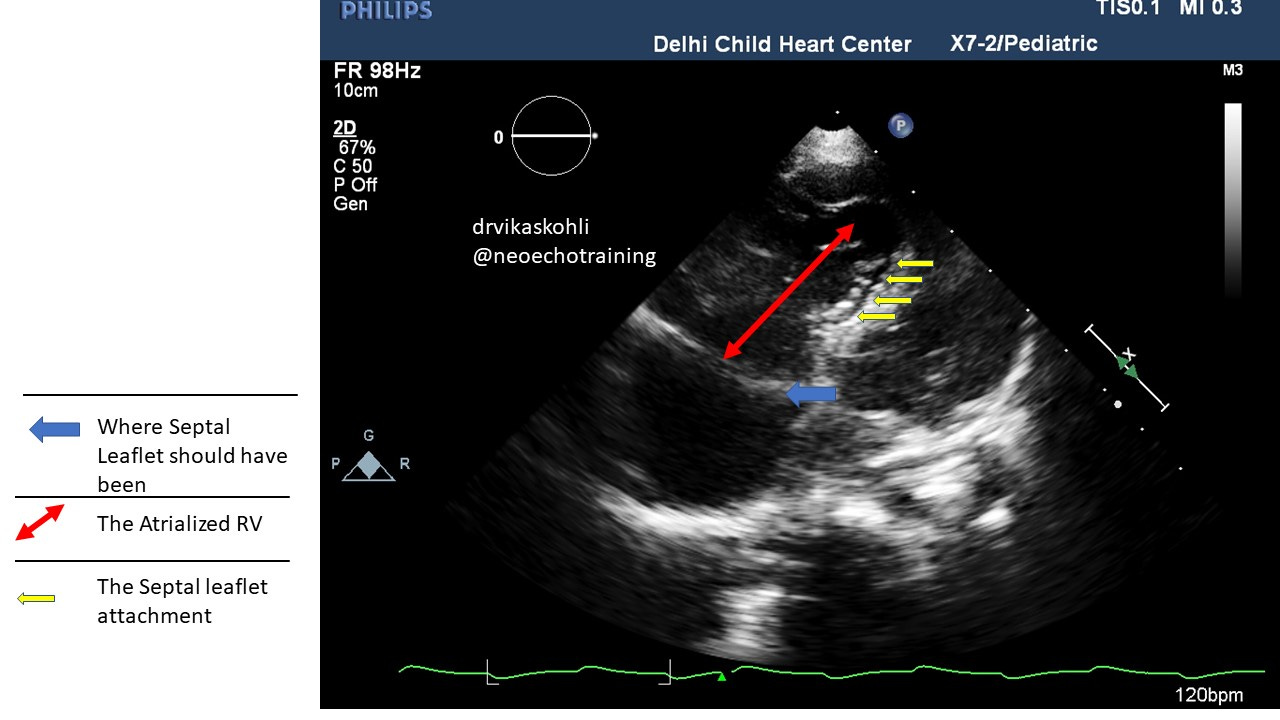

c). The Septal leaflet if you look carefully ( and in the picture below) is stuck to the septum and moves only near the apex of the RV:

The RV from the true tricuspid attachment to the new septal leaflet attachment is referred to as Atrialized RV.